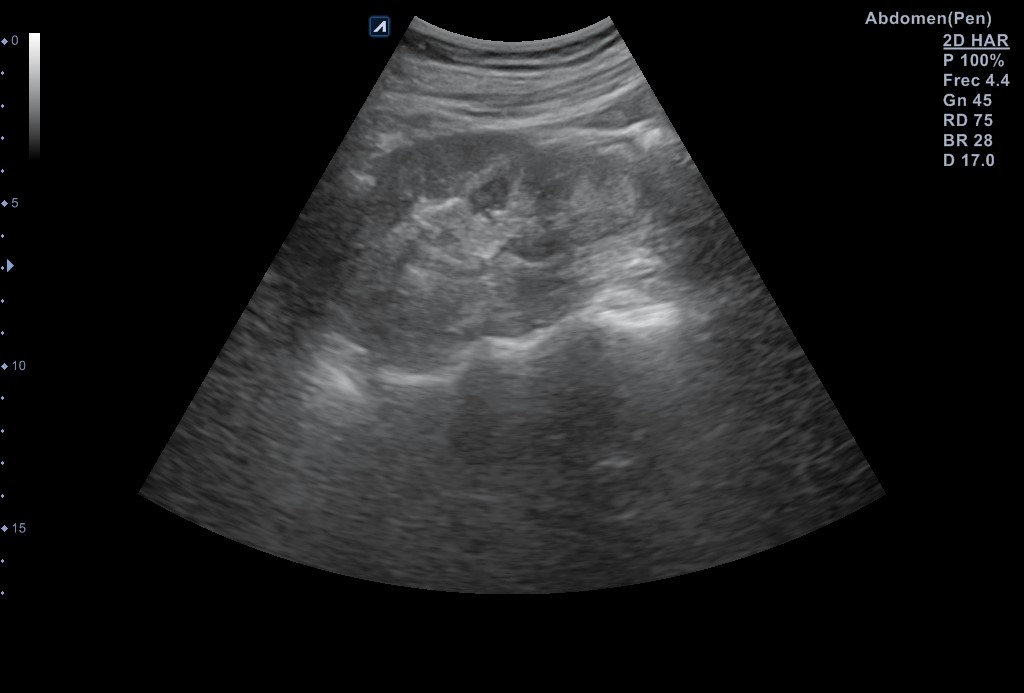

Ecografía vía urinaria: se evidencia una lesión en el tercio inferior de riñón izquierdo de aspecto quístico multiseptada, con polo sólido compatible con quiste Bosniak 3 de 30 x 29 mm que no capta Doppler, compatible en este contexto con absceso renal o neoformación renal. No otras alteraciones en resto del tracto urinario.

Se reevalúa a la paciente en consulta 2 semanas después, que refiere mejoría sintomática. Se repite la ecografía evidenciándose imágenes de riñón izquierdo sano y ausencia de la lesión previamente descrita.